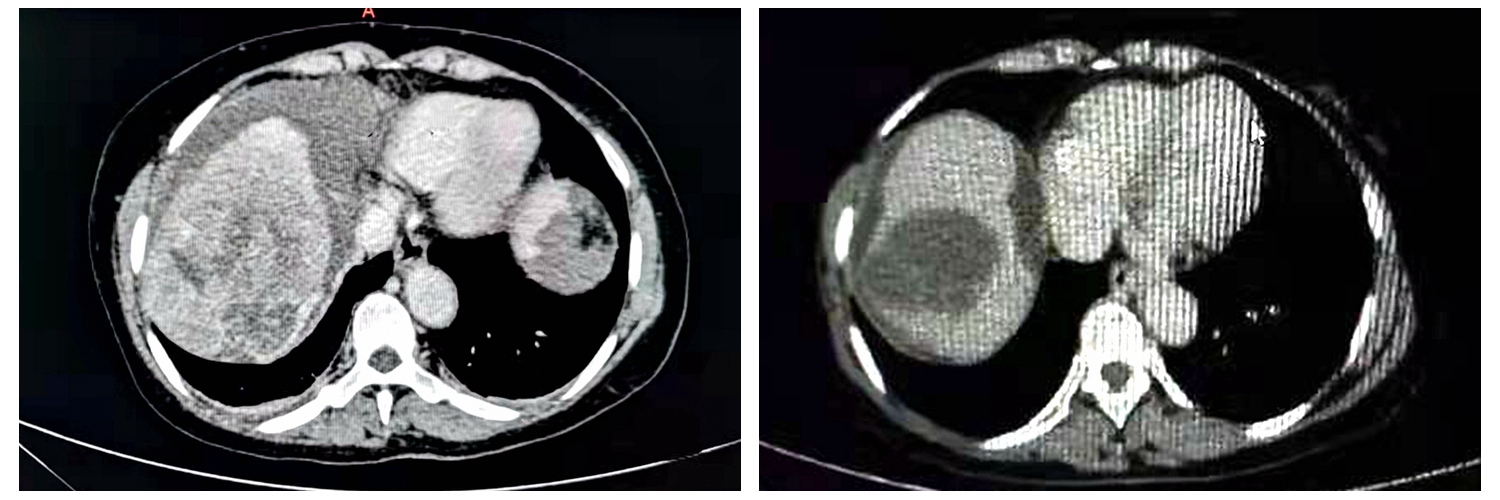

67岁的李阿姨4个月前无明显诱因出现了腹胀、食欲差,在当地医院查超声发现肝占位,由于有乙肝病史,李阿姨及家属十分担忧,随后转诊到驻马店市中心医院肿瘤内二科住院治疗。在完善相关检查后发现患者甲胎蛋白显著升高上腹部增强CT提示肝癌伴有门静脉癌栓、腹水确诊属肿瘤中晚期。

经过两个周期的介入治疗,患者的肿瘤就明显得到控制,肿瘤标志物甲胎蛋白显著下降,由入院时的六千多下降到了二百多,腹水消失,门脉癌栓消退,再通过内科的靶向治疗及免疫治疗后,患者甲胎蛋白恢复正常,肿瘤活性消失,临床评价疗效达到完全缓解。